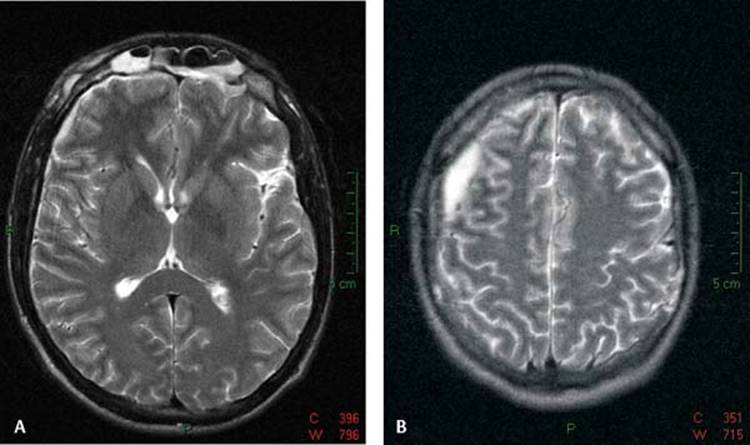

Intracranial complications are less frequent than orbital complications and are seen more with frontal or sphenoidal sinusitis. Intracranial spread of the infection should be suspected when a change in neurological or mental status is evident. Other symptoms and signs are high fever, severe headache, nausea and vomiting, seizures and signs of increased intracranial pressure. Neurological and/or neurosurgical consultation is warranted in case a patient with sinusitis develops one of the above issues. Intracranial complications include meningitis, epidural abscess, subdural empyema (Figs. 8.5 and 8.6A, B), and brain abscess. Frontal sinusitis may spread to the sinus bony walls and result in an osteomyelitis of the anterior and/or posterior tables. This may result in a frontal bone SPA and forehead cellulitis (Pott's puffy tumor).25

Figure 8.6 (A) Magnetic resonance image T2 axial view of frontal sinusitis associated with subdural empyema and (B) Magnetic resonance image T2 axial superior section showing subdural empyema.